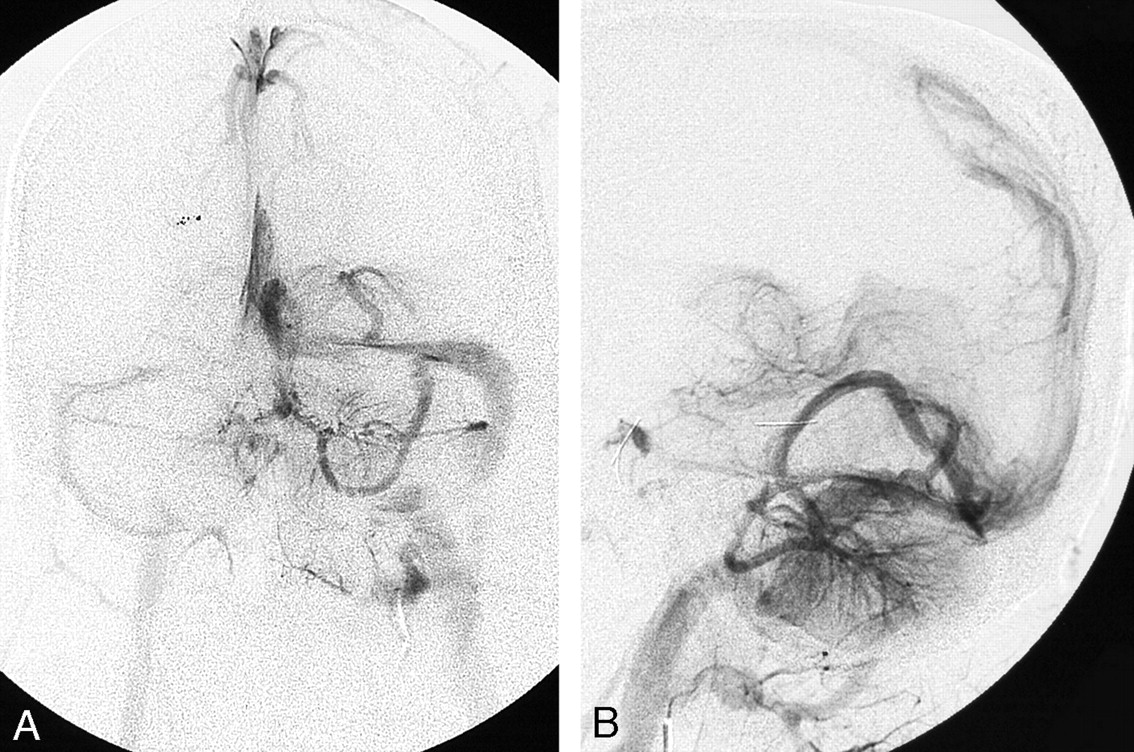

Intracranial vascular anomalies were identified in 22 patients (67%) (Table 2). In 14 patients (60%), these were ipsilateral to the orbital involvement. Nine patients had bilateral intracranial vascular anomalies with the predominant abnormality on the same side as the orbit. The following intracranial vascular anomalies were identified: 20 DVAs (60.6%) (Figs 1to 3), 2 CCMs (6.1%) (Fig 4), 4 dural AVMs (12.1%) (Figs 5 and 6), 1 pial AVM (3%), and 1 SP (3%). Two patients had arterial shunts into the extracranial vascular malformation (Fig 7). There were also 3 jugular venous abnormalities (9%). Ipsilateral anomalies of the jugular vein included absent or occluded jugular veins associated with a hypoplastic or occluded transverse sinus in 2. A varix of the vein of Galen was seen in one of these patients. Dural enhancement in the middle cranial fossa, adjacent to the sphenoid bone, was seen in 5 patients (15.2%).

A and B, Posterior fossa DVA in another patient is confirmed angiographically. Frontal (A) and lateral (B) venous phase of left vertebral angiogram shows the left cerebellar and left occipital DVAs draining into the left transverse sinus.